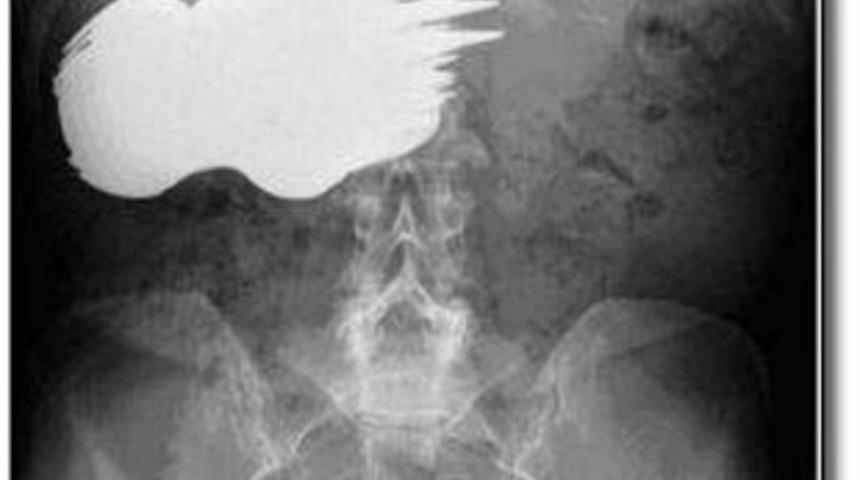

52 yaşındaki Margaret Daalman'ın karnından tam 78 parça kaşık ve çatal çıktı. İlginç olan da kadının bunları yutmasıydı. Önce 50 tane yutan kadın daha sonra 28 tane daha yuttu.